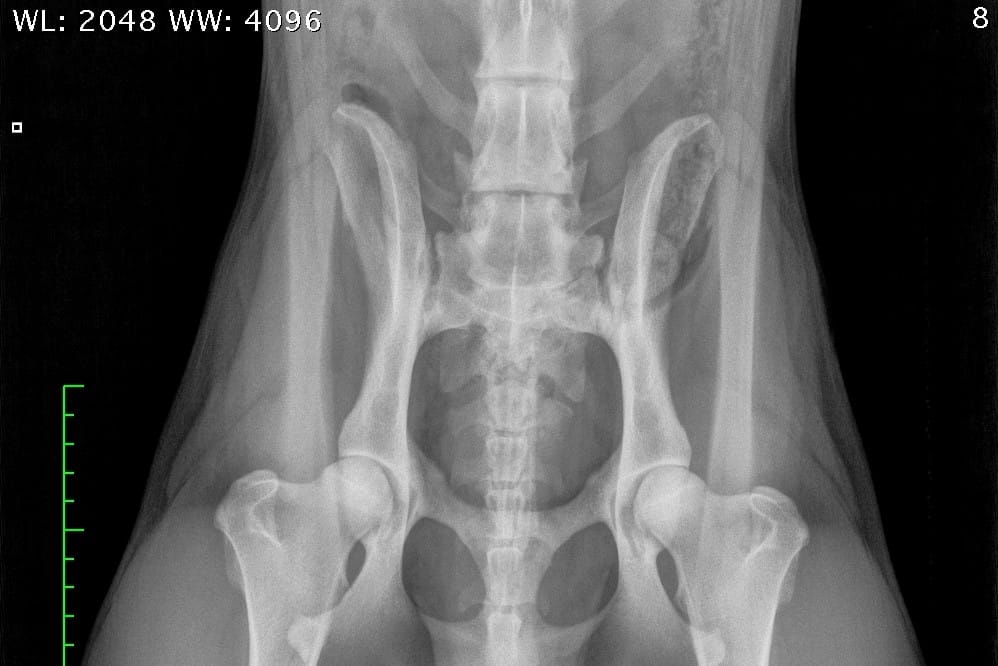

LTV4; 8 lumbar vertebras. L8 shaped like a lumbar vertebra and it has complete spinous process.

The second largest score 20% is LTV4 (6 or 8 lumbar vertebras). Most of these dogs have 8 lumbar vertebras (lumbarization).